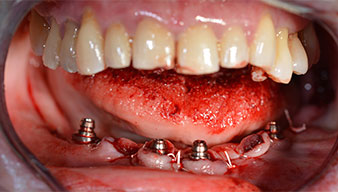

Nach der Entfernung der Unterkiefer-Restbezahnung erfolgte die krestale Schnittführung von Regio 37 bis Regio 47.

Zunächst wurde das Foramen mentale als limitierende anatomische Struktur dargestellt und die krestale Kortikalis mit dem geraden Handstück und einem großen Rosenbohrer geglättet (Abb. 4).

Um die Divergenz der distalen Implantate auszugleichen, werden abgewinkelte Abutments (35 Grad) eingeschraubt, sodass die Austrittsprofile sämtlicher Implantate möglichst senkrecht zur Kauebene stehen. Dies ist Voraussetzung, um die provisorische und später auch die endgültige Versorgung okklusal verschrauben zu können (Abb. 15 und 16).

Implantate

Abb. 15

Abb. 16

Im Anschluss erfolgt die Abformung und Bissnahme, sodass die Zahntechniker umgehend mit der Anfertigung der provisorischen Arbeit beginnen können. Diese wird im Anschluss am gleichen Tag eingeschraubt (Abb. 17 und 18).

Abb. 17

Abb. 18